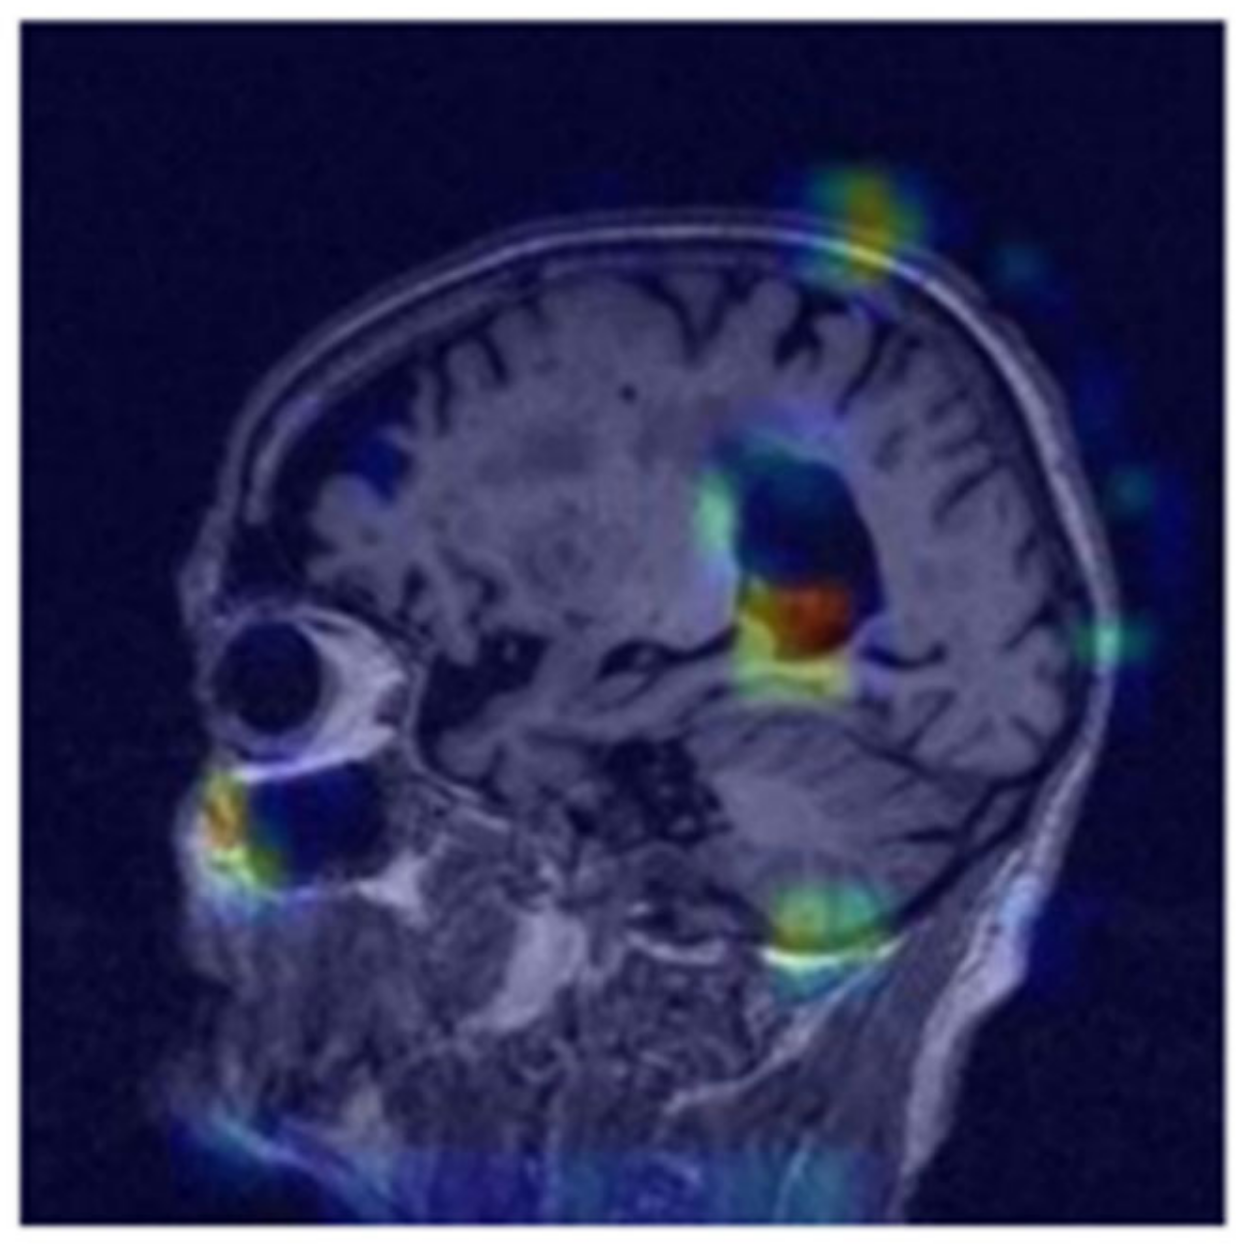

where ReLU, the rectified linear unit activation function, sets negative values to zero, k   is the sum of all activation maps, w k ( c ) represents the weights relative to the k -th activation map for class c , and A k is the k -th activation map. The ultimate standardized heat map accentuates the areas upon which our deep learning algorithm relies to provide predictions [8,9,25,26,27]. We employed a channel-wise self-attention mechanism to highlight significant features within each channel of the input tensor (Figure 8). This mechanism was accomplished through two convolutional layers with (1, 1) kernels that generate an attention map, which is then element-wise multiplied with the input tensor. The initial convolution layer, followed by a ReLU activation, formed an intermediate representation, while the subsequent convolution layer with a sigmoid activation created the attention weights. These weights adjust the emphasis on different channels, enabling the model to enhance or reduce specific features, thereby improving the learning process and overall performance [24,28,29,30].

Figure 8. Jet heatmap of positive values using self-attention for class-specific interpretability with gradient-weighted class activation mapping. The highest level of intensity in the heatmap is observed in close proximity to the hippocampus.